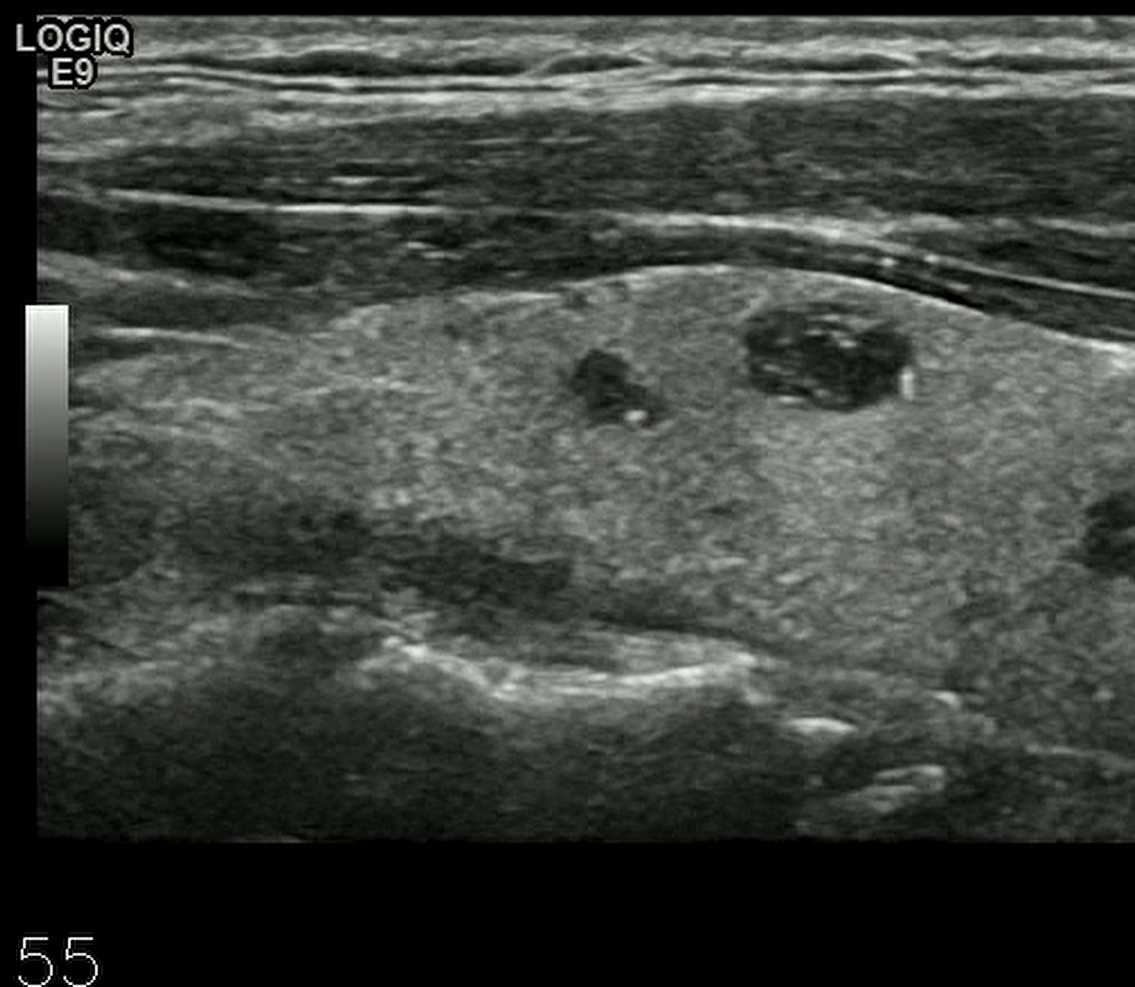

处理前: